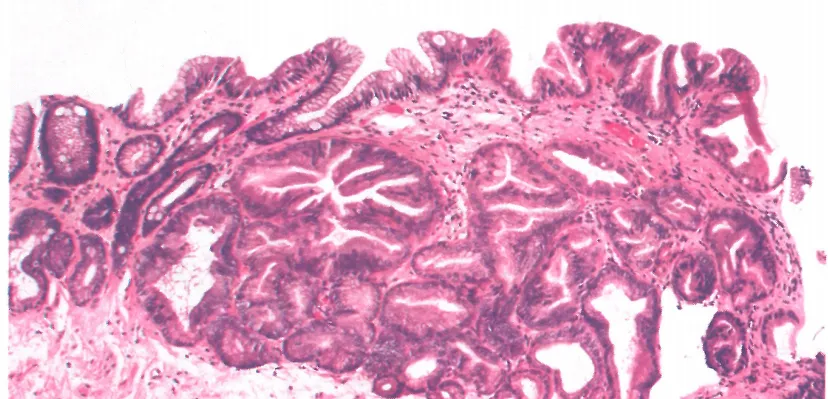

• 黏膜内浸润性肿瘤/黏膜内腺癌:侵犯黏膜固有层或黏膜肌层的肿瘤。

• 与HGD的区别在于独特的结构异常:腺体拥挤、过度分支和芽生现象,无论是否存在促结缔组织反应;

• 单细胞浸润、小梁状生长、腺内坏死碎片、不规则(爬行)融合或小型退行性腺体可能是有助于诊断的特征性表现。